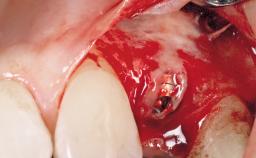

Placement Protocol Immediate implant placement

Socket Morphology Single-root socket

Socket Integrity Damage to one or more bone walls

Bone Volume Damage to one or more socket walls

Anatomic Risk Low

Complexity Moderate

Risk of Complications High